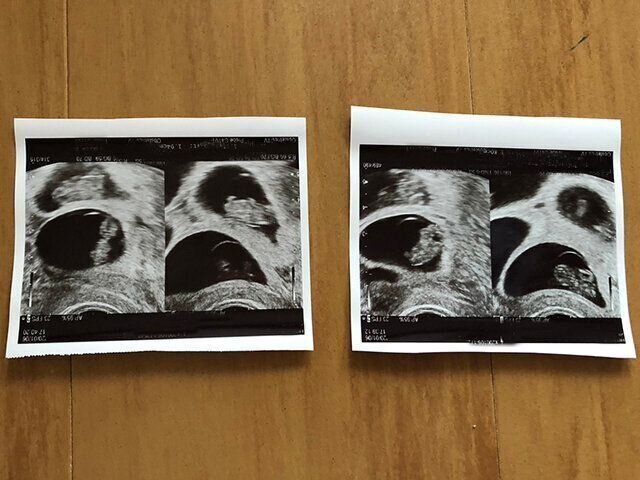

妊娠29週で帝王切開。約30人の医師らに見守られながら4つ子が誕生

「妊娠中は切迫早産になり、子宮口を縛る手術をしたり、おなかの張りを抑えるために、入退院を繰り返しました。妊娠24週〜出産までは管理入院をしました。コロナ禍真っ只中で、入院中は家族との面会が一切禁止でした。出産まで誰とも会えず不安な気持ちを抱えて、1人で産まなければならなかったのがつらかったですね。けれども、私自身は先生からも驚かれるぐらい、動き回ってバクバク食べれる元気な妊婦だったので、それが救いでした(笑)。最終的にウエスト周りは120センチになりました。

私は『とにかく子どもたちをおなかの中に長く居させてあげたい』という一心でした。『とりあえず27週!』『次は28週!』『あともう1週間!』……と目標を掲げ、日記に書き記しながら、1日1日を乗り切りました。しかし、すべてが予定通りとはいかず、『おなかの中で上にいる子が下にいる子を圧迫し、下の子の心拍が低下しつつある』という判断で、29週に帝王切開となりました」(よつは)

妊娠当時の日記